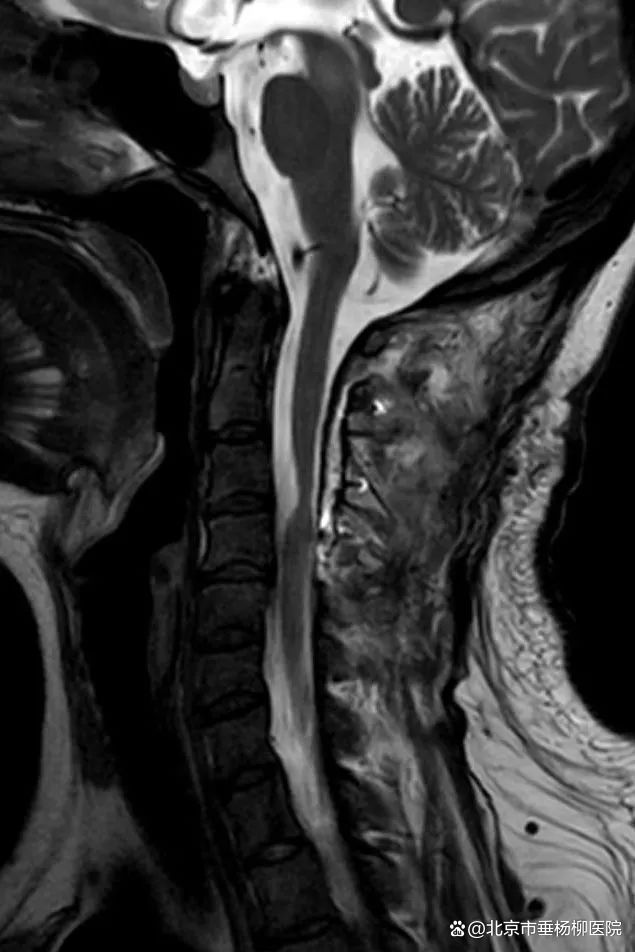

为进一步诊治,杭女士辗转前来北京市垂杨柳医院神经外科寻求帮助。神经外科主任张锟带领全科医生就杭女士的病情展开讨论,认为患者慢性病程,逐渐加重,表现为颈神经根痛症状。颈椎核磁显示颈3-4水平椎管内脊髓外囊性病变,位于脊髓腹侧面,边界清楚,呈长T1长T2信号,脊髓明显受压变扁,打药后无强化。诊断考虑为良性囊性病变,肠源性囊肿可能性最大,为一种少见的先天性病变。手术指征明确,手术难点及风险在于,病变位于高颈髓水平且位于脊髓腹侧面,从后方入路显露病变时需牵拉脊髓及神经根,术后可能出现高位截瘫及呼吸困难。此外囊肿壁可能与脊髓黏连紧密,无法全切病变而导致复发。

▲颈椎核磁矢状位显示

颈3-4水平椎管内脊髓外囊性病变

位于脊髓腹侧,呈长T1长T2信号

脊髓明显受压变扁